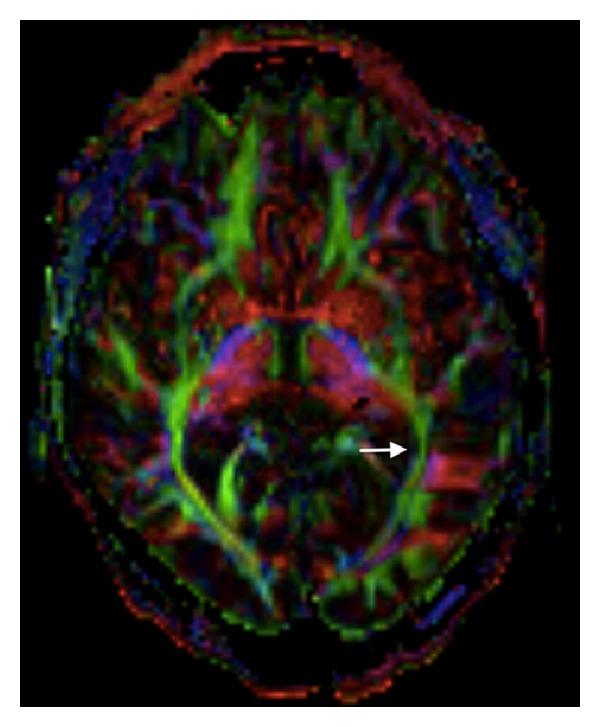

Background. Spontaneous intracerebral hemorrhage (ICH) is common and causes significant mortality and morbidity. To date, optimal medical and surgical intervention remains uncertain. A lack of definitive benefit for operative management may be attributable to adverse surgical effect, collateral tissue injury. This is particularly relevant for ICH in dominant, eloquent cortex. Minimally invasive surgery (MIS) offers the potential advantage of reduced collateral damage. MIS utilizing a parafascicular approach has demonstrated such benefit for intracranial tumor resection. Methods. We present a case of dominant hemisphere spontaneous ICH evacuated via the minimally invasive subcortical parafascicular transsulcal access clot evacuation (Mi SPACE) model. We use this report to introduce Mi SPACE and to examine the application of this novel MIS paradigm. Case Presentation. The featured patient presented with a left temporal ICH and severe global aphasia. The hematoma was evacuated via the Mi SPACE approach. Postoperative reassessments showed significant improvement. At two months, bedside language testing was normal. MRI tractography confirmed limited collateral injury. Conclusions. This case illustrates successful application of the Mi SPACE model to ICH in dominant, eloquent cortex and subcortical regions. MRI tractography illustrates collateral tissue preservation. Safety and feasibility studies are required to further assess this promising new therapeutic paradigm.

背景。自发性脑出血(ICH)很常见,会导致严重的死亡率和发病率。迄今为止,最佳的药物和手术干预仍不明确。手术治疗缺乏明确益处可能归因于不良手术效果、侧支组织损伤。这在优势功能区、明确的皮质区的脑出血中尤为相关。微创手术(MIS)具有减少侧支损伤的潜在优势。采用束旁入路的MIS已在颅内肿瘤切除术中显示出这种益处。方法。我们报告一例通过微创皮质下束旁经沟入路血肿清除术(Mi SPACE)模型清除优势半球自发性脑出血的病例。我们利用本报告介绍Mi SPACE并探讨这种新型MIS模式的应用。病例介绍。该患者表现为左侧颞叶脑出血和严重的完全性失语。通过Mi SPACE方法清除血肿。术后重新评估显示有显著改善。两个月时,床边语言测试正常。磁共振成像纤维束成像证实侧支损伤有限。结论。本病例说明了Mi SPACE模型在优势功能区、明确的皮质区和皮质下区域脑出血中的成功应用。磁共振成像纤维束成像显示侧支组织得以保留。需要进行安全性和可行性研究以进一步评估这种有前景的新治疗模式。